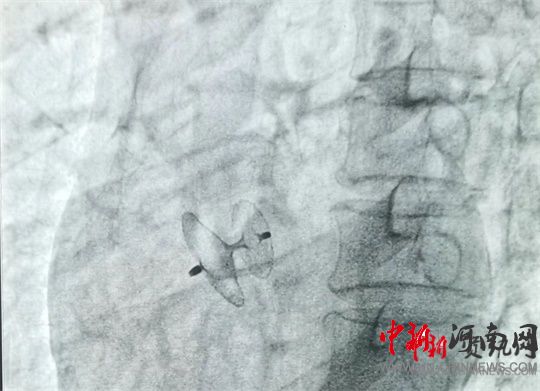

岳軍帶領(lǐng)團(tuán)隊(duì)將封堵器通過(guò)股靜脈送至卵圓孔處,展開(kāi)封堵傘,使其與卵圓孔完美契合,成功封堵住缺口。經(jīng)床旁彩超證實(shí),無(wú)殘余分流,手術(shù)過(guò)程十分順利,全程僅用時(shí)60分鐘。術(shù)中及術(shù)后,患者均未出現(xiàn)不良反應(yīng),術(shù)后12小時(shí)即可下床活動(dòng)。